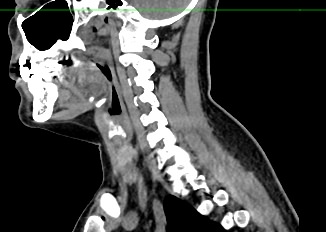

Компьютерная томография является современным высокотехнологичным методом диагностики заболеваний щитовидной железы, основанном на использовании рентгеновского излучения. Процедура отличается быстротой, безболезненностью и проводится без нарушения целостности кожи и расположенных под ней тканей.

В наших центрах обследование щитовидной железы выполняется на современных мультиспиральных томографах TOSHIBA AQUILION, оснащенных увеличенным количеством сверхчувствительных детекторов, позволяющих производить 64 или 128 срезов с минимальной толщиной от 0,5 мм.

Инновационные возможности аппаратов обеспечивают получение множества послойных снимков высокого качества и построение на их основе трехмерной модели органа. Кроме того, аппаратура позволяет за счет сокращения времени сканирования минимизировать лучевую нагрузку на пациента.

КТ щитовидной железы часто используется в диагностике доброкачественных и злокачественных опухолей железы, оценки распространенности процесса, поэтому для улучшения визуализации патологических очагов дополнительно применяется внутривенное болюсное контрастирование. Методика контрастирования позволяет увидеть на снимке опухоли минимальных размеров за счет того, что контраст избирательно накапливается в измененных тканях и обеспечивает яркое изображение патологического очага на фоне здоровых окружающих тканей.